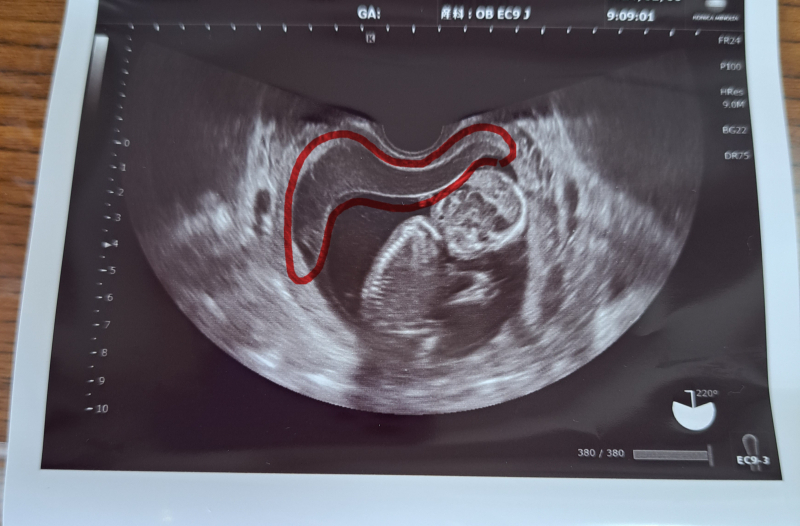

2週間前に突然職場で生理2日目くらいの鮮血の出血があり、絨毛膜下血腫とのことで自宅安静しておりました。1週間前に受診したところ、出血の原因となっていた血腫はなくなっておりましたが、お腹が張った跡だという空間のようなものが赤ちゃんの近くに映っていました。その時は医師から普段通りの生活はしていいとのことで、仕事は休んでいましたが上の子もいるため多少動いたりはしていました。その間、茶おりは続いておりお腹の張りもありました。そして今日また受診したところ、画像のような感じでお腹が張った跡である空間が大きくなってしまっていました。(赤く囲っています)そしてまた1ヶ月自宅安静になってしまいました。

血腫が大きくなってしまったのは動きすぎが原因なのでしょうか??